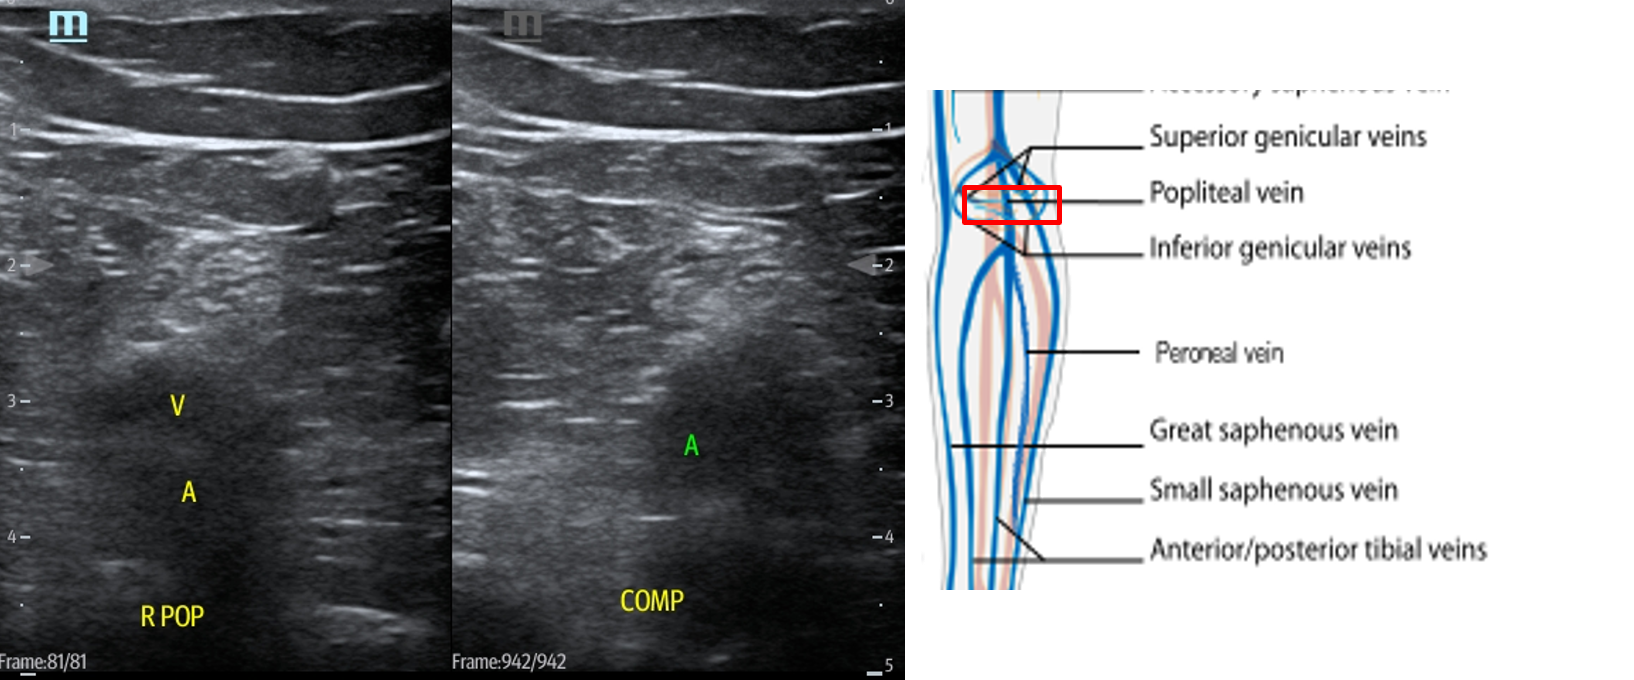

- In the popliteal region, you should see the popliteal vein (PV) superficial to the popliteal artery (PA). (Fig. 14) If you see more than one artery and one vein, slide the transducer proximally until you see the PV and PA. When you have this view, compress as before.

- Figure 14. Compression of the popliteal vein in the popliteal fossa with transducer orientation indicated (red rectangle).

- Slide the transducer distally until you see the PV trifurcate into the PTV, ATV and peroneal vein. (Fig. 15) Compress each of these veins. This constitutes completion of evaluation of “region 2.”

- Figure 15. Compression of the PTV, ATV and peroneal vein in the distal portion of the popliteal fossa just before they converge into the popliteal vein with transducer orientation indicated (red rectangle).